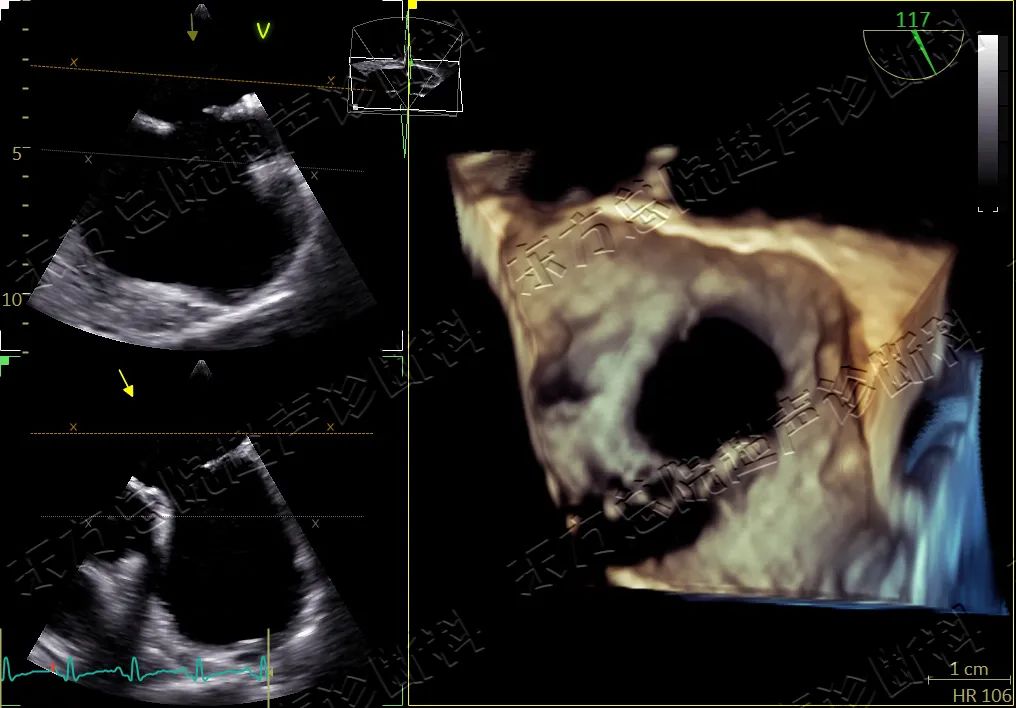

▲房缺四维成像图